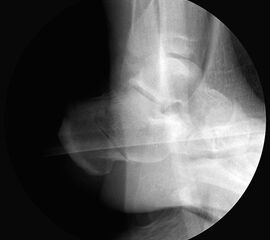

Bei Rückfussfehlstellungen ist meist eine knöcherne Korrektur des Kalkaneus indiziert. Dabei wird das Fersenbein im Bereich des Tuber calcanei durchtrennt und der Achillessehnenansatz nach medial oder lateral geschoben. Zusätzlich ist eine Rotation des Tuber möglich, wodurch sich der Korrektureffekt noch verstärkt. Durch die Wahl der Osteotomieebene kann die Verscheibung mit einer Verlängerung oder Verkürzung des Fersenbeins kombiniert werden. Die Osteosynthese erfolgt typischerweise durch perkutan eingebrachte Schrauben.

Bildwandler Bildgebung.

Bildverstärker.